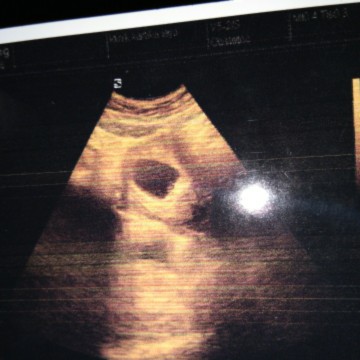

usia 8 minggu janin belum terlihag

Kalau 8 minggu harusnya sdh terlihat, tapi ditunggu aja 2 minggu lagi atau option lain usg transv.

Sudah ada kantong janin nya blm? Kalo sdh ya gpp. Normal